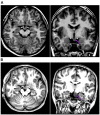

Purpose: There are few studies on the glucose metabolic characteristics of the extra-hypothalamic cortex in the hypothalamic hamartomas (HH). A comprehensive understanding of pathogenic progression of the disease is required from the perspective of cortical metabolism; therefore, we aimed to characterize metabolic characteristics of extra-hypothalamic in HH patients. Methods: We investigated the metabolic characteristics of 16 HH patients, all of whom underwent epilepsy evaluation at Xuan Wu Hospital between 2017 and 2019. The lateralization and cortical distribution pattern of hypometabolism was assessed and related to HH mass neuroanatomy on magnetic resonance imaging (MRI) as well as scalp-electroencephalogram (scalp-EEG) abnormalities. Furthermore, asymmetry measurements of region of interest (ROI) in the temporal cortex (hippocampal formation, amygdala, and lateral temporal neocortex) were quantitatively assessed based on the normalized average positron emission tomography (PET) voxel values. The surgery prognosis was assessed using the International League Against Epilepsy (ILAE) classification system. Results: The lateralization of hypometabolism in global visual ratings was consistent with the HH mass lateralization seen on MRI. Cortical hypometabolism showed three patterns depending whether the HH mass involved mammillary bodies, middle hypothalamus nucleus, or both. The three patterns were hypometabolism of the mesial temporal cortex with symptom of mesial temporal epilepsy (3/16, pattern I), lateral temporal, and extratemporal (frontal or parietal) cortex with symptom of neocortex temporal or frontal epilepsy (5/16, pattern II), and mesial and lateral temporal cortex and extratemporal (frontal or parietal) cortex with varied symptoms (8/16, pattern III), respectively. A significant difference in PET voxel values was found between bilateral hippocampal formation (P = 0.001) and lateral temporal neocortex in the third group (P = 0.005). We suggest that the hypometabolic characteristics of the extra-hypothalamic cortex in HH patients have three patterns. The final cortical hypometabolic pattern depends on the neuroanatomic location of the HH mass and was consistent with the main involved cortex of the interictal and ictal discharges. The third hypometabolic pattern with the most extensive cortical hypometabolism has a poorer prognosis.